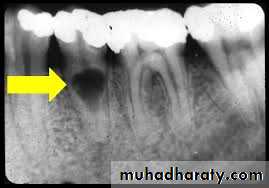

- Size of the lesion:

Pulp pathosis→periapical lesion(abcess →granuloma →cyst)

(The smaller the radiographic emage, the more likely the diagnosis is granuloma is correct)

According to Lalonde:

0-1cm →70% granuloma-30% cyst.

1-2cm →40% granuloma-60% cyst.

↑2cm →100% cyst.

Tay etal demonstrated that the success of conservative endodontic therapy deminished with the increased size of the periapical lesion